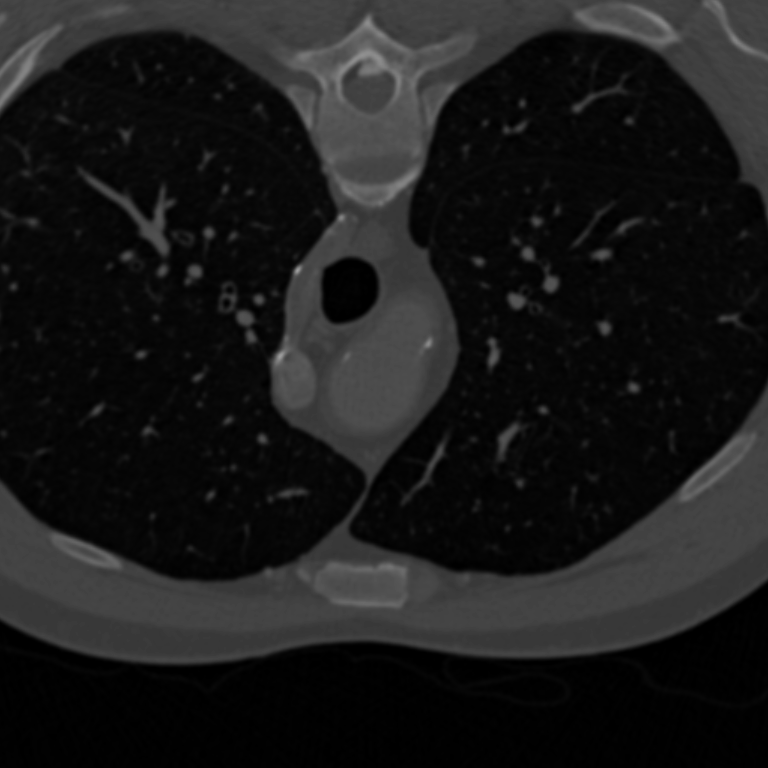

Use

opento remove small objects in the lungs.>>> opened = im.open(kernel_size=15) >>> opened.plot(**kwargs)